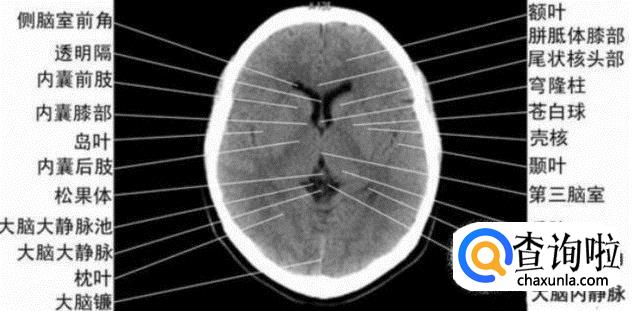

- 013

侧脑室体部层面

由额、颞、枕叶构成,两侧侧脑室体部之间为透明隔,外侧为尾状核和体部。侧脑室后角(枕角)可不对称,室内可见脉络丛钙化。中线处可见大脑纵裂池和大脑镰。

- 014

侧脑室上部层面

内侧壁侧脑室体部被胼胝体分开,侧脑室体部的外方为顶叶,顶枕沟及中央沟将大脑为为额、顶、枕叶。

- 015

大脑皮质下部层面(半卵圆中心层面)

在胼胝体和侧脑室上方,大脑镰自前向后贯穿中线。白质部分为半卵圆中心,额叶范围缩小,顶叶所占比例扩大,枕叶基本消失。

半卵圆中心:位于胼胝体上方,由左右大脑半球髓质形成的有髓纤维,对称位于大脑镰两侧区域。